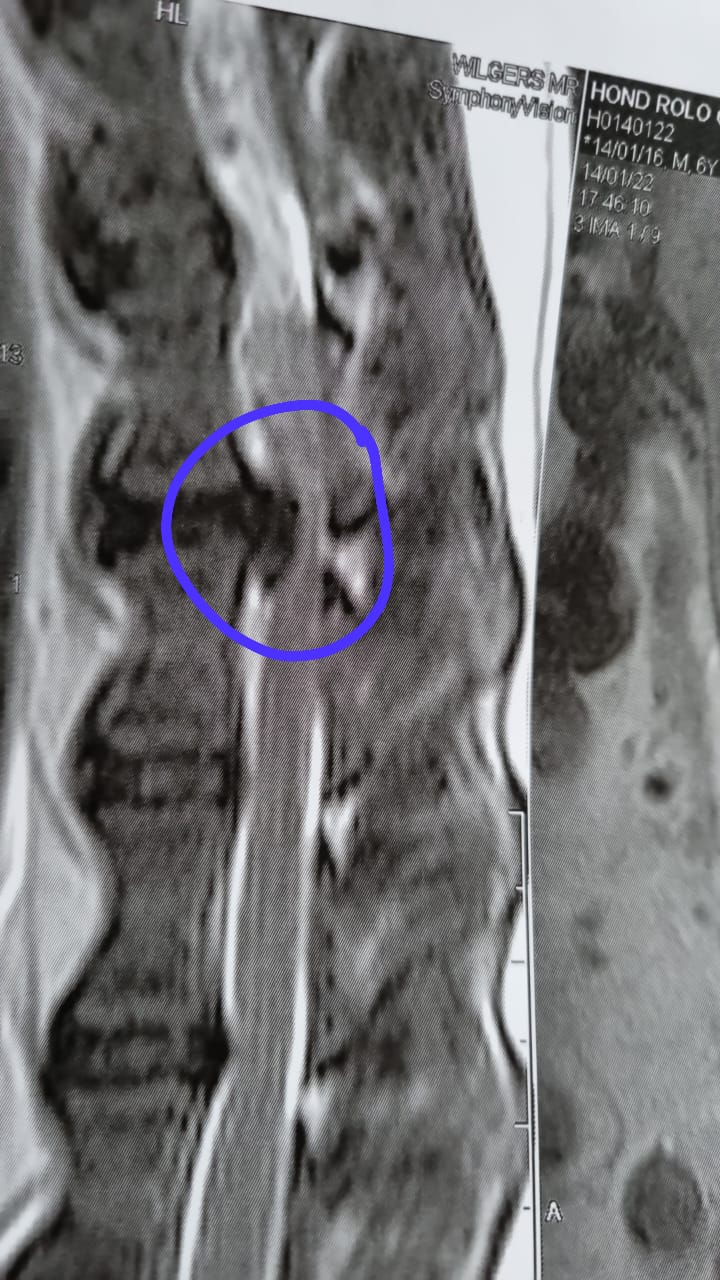

Caring for Pets with Back Problems At Accuvet Veterinary Hospital, we know how scary it can be when your pet suddenly can't walk, is in pain, or just isn't acting like themselves. Spinal issues—especially Intervertebral Disc Disease (IVDD)—can be serious, but with the right care, many pets can return to a happy, active life. What is IVDD? IVDD happens when the discs between the bones in your pet’s spine slip or burst, putting pressure on the spinal cord. This can cause anything from mild pain to full paralysis. It's most common in breeds like Dachshunds, French Bulldogs, and Bassets, but can affect many dogs. Signs to watch for:

How we can help If we suspect IVDD or another spinal issue, we’ll start with a full examination and discuss the best way forward. Some pets improve with rest and medication, but others may need spinal surgery to relieve the pressure on the spine. At Accuvet, we offer: